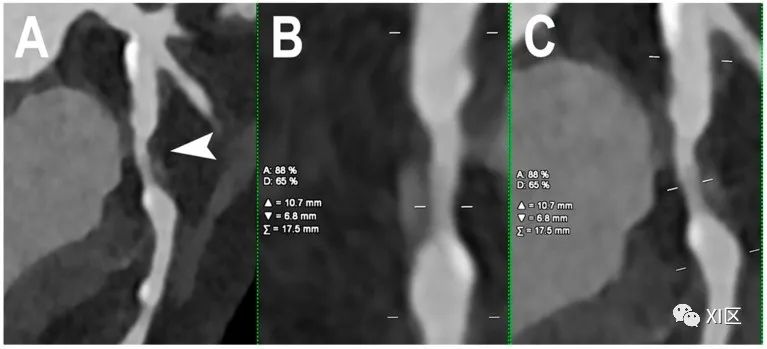

阻塞性CAD的心脏PCCT示例。图中显示的是一个左旋支动脉狭窄的病例,其原因主要是非钙化的动脉粥样硬化斑块,并伴有不明显的正性重构((A);箭头所指)。本例采用0.4mm层厚。对狭窄处的定量评估((B、C);狭窄处的正交纵向视图)显示,管腔直径缩小了65%,管腔面积缩小了 88%。